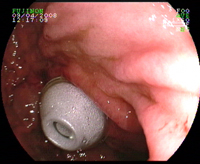

Clip ouvert en bout d'endoscope